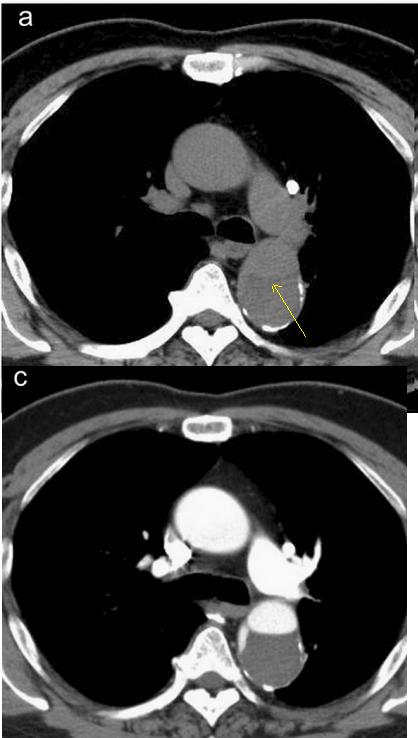

总结

血管钙化内移,高度警惕动脉夹层,但不是绝对的!

血管内线样阴影,警惕警惕动脉夹层。记住,鲁迅说了,大约肯定有血管内线样阴影,才要怀疑动脉夹层,如果隐隐约约不肯定,不要过度诊断!

下图是:大约肯定有血管内线样阴影!

图25

下图是:隐隐约约不肯定有血管内线样阴影!

图26